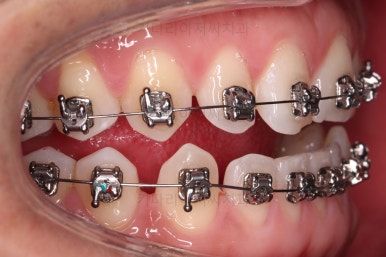

초진 시의 입안 모습입니다.

어금니가 빠져서 결손치아가 있고 치아 사이에 틈새도 있어서 교정치료도 함께 원한다고 내원해 주셨어요.

사진에서 보시는 바와 같이 윗니 1개, 아랫니 1개의 결손 부위가 보입니다.

윗니 어금니 중에는 신경치료를 마무리 못하고 임시재료로 메꿔뒀던 부위도 보이고요.

교정장치를 부착하고 충치치료는 별개로 진행되었어요.

이번에 선택하신 장치는 자가결찰(철사를 잡아주는 뚜껑이 자체적으로 달려있는) 메탈(금속)장치이며 엠파워 메탈이라고 하는 장치입니다.

세라믹에 비해 많이 보인다는 단점이 있지만 저렴하고 튼튼한 관리가 약간은 더 편하다는 장점이 있어요.